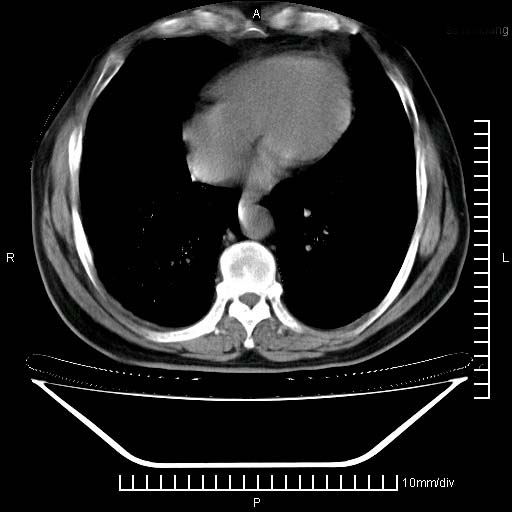

标题: CT24043:胸部增强:男性,60岁

既往肺结核,近10几天,咳嗽,咳痰,右侧胸痛,疼痛较明显,右上肺斑块考虑结核灶胸膜粘连,增强,可惜动脉期没有定好,未见强化,可延迟4分后又见较明显强化,中心见低密度影,如果说结核是边缘强化,可这个灶强化的面积挺大的,让人很挠头。

延迟4分后

[img][/img]